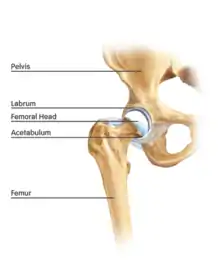

The hip is essentially a ball and socket joint. It consists of the head of the femur (the ball) and the acetabulum (the socket). Both the ball and socket are congruous and covered with hyaline (or articular) cartilage, which allows smooth, almost frictionless gliding between the two surfaces. The edge of the acetabulum is surrounded by the acetabular labrum, a fibrous structure that envelops the femoral head. (See fig. 1) The labrum acts as a seal, or gasket, around the femoral head. However, this is not its only function, as it has been shown to contain nerve endings, which may cause pain if damaged.[18] The blood supply of the labrum has also been demonstrated.[25] The joint itself is encompassed by a thick, fibrous joint capsule, which is lined by synovium. The ligaments that keep the hip joint in place are in fact, thickened areas of joint capsule, rather than distinct structures. The synovium generates fluid that lubricates the joint; in that fluid are the nutrients needed to keep the cartilage cells alive. A total of 27 muscles cross the hip joint, making it a very deep part of the body for arthroscopic access. This is one reason why hip arthroscopy can be quite technically demanding.